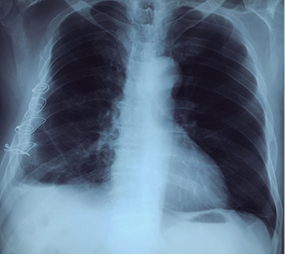

Se presenta el caso de un paciente de 72 años de edad con historia de haber sufrido caída de un árbol 21 días antes. Fue atendido en un hospital departamental donde le realizaron radiografía de tórax (Figura 1), que mostraba fracturas simples de varios arcos costales del hemitórax derecho con hundimiento de la parrilla costal. La TAC de tórax (Figura 2) muestra fracturas del 3o al 9o arcos costales derechos, con borramiento del ángulo costodiafragmático y colapso pulmonar basal del mismo lado.

Figura 2: TAC de tórax de ingreso. Se observa desplazamiento de arcos costales fracturados, hemotórax retenido.